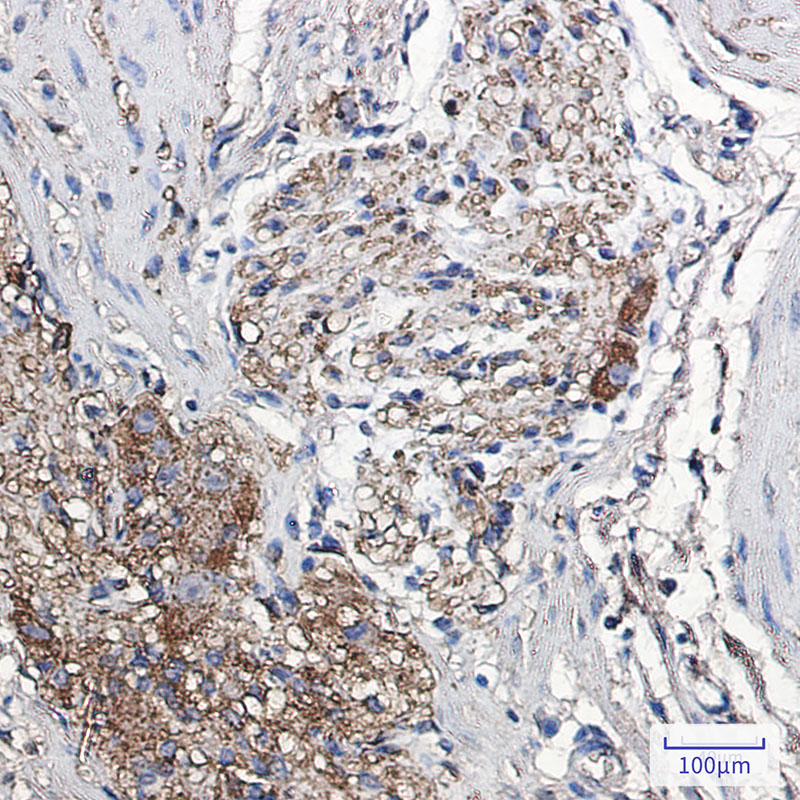

Immunohistochemistry analysis of paraffin-embedded Human colon cancer using Alphasynuclein antibody.High-pressure and temperature Sodium Citrate pH 6.0 was used for antigen retrieval.